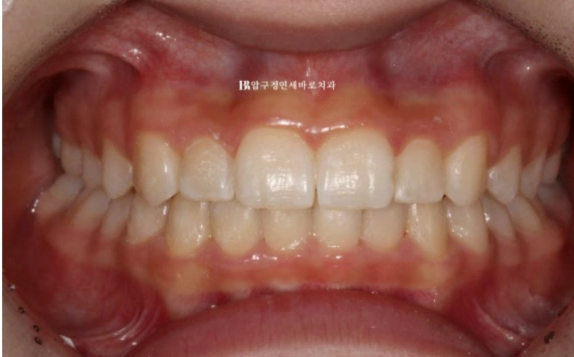

그리고 지난 달 치료가 마무리 되었습니다.

깊게 물리던 과개교합과 덧니가 깔끔하게 치료가 되었습니다.

24.02